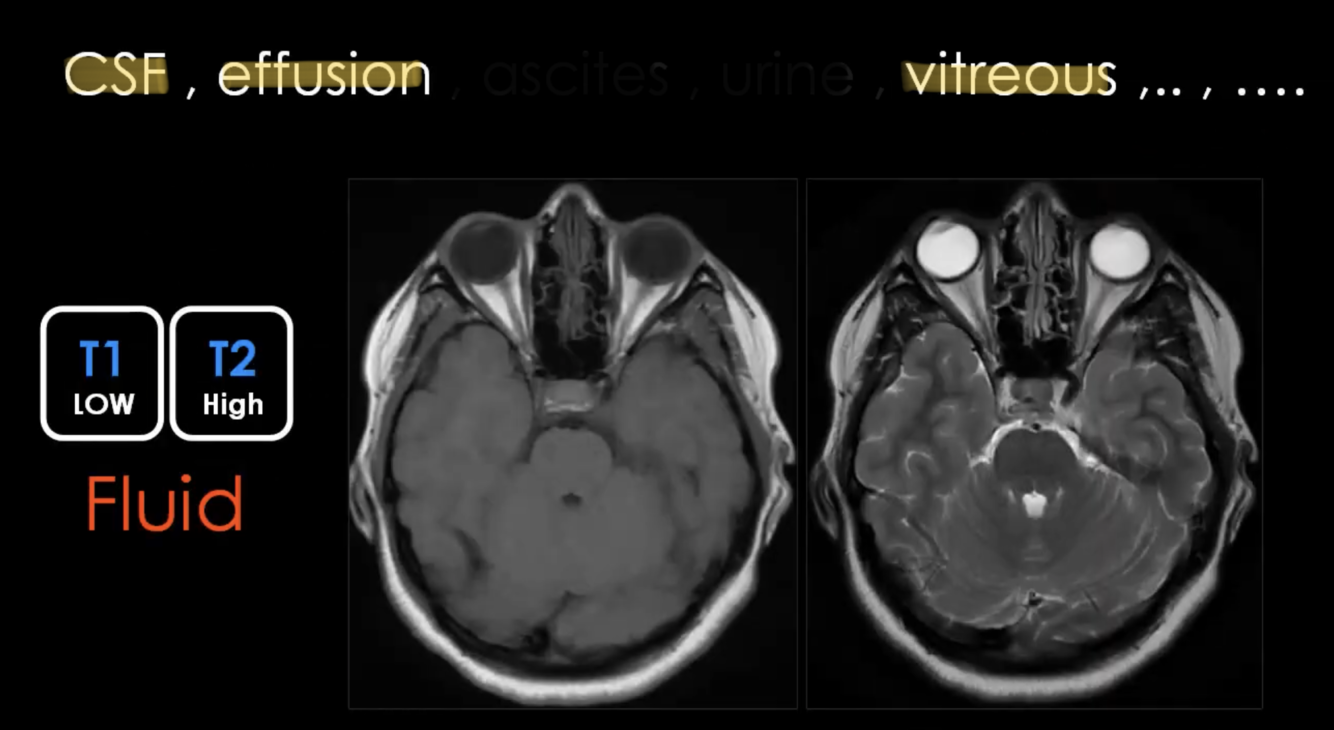

What is LOW T1 / HIGH T2?